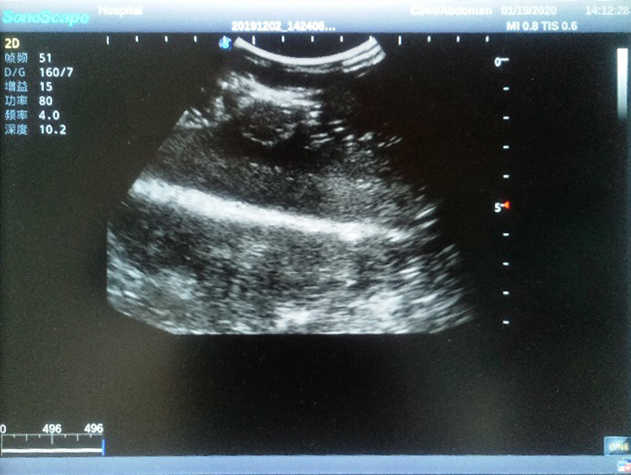

4) Biomimetic material allowing users to see clear and real normal tissues and space-occupying lesions that are hyperechoic, hypoechoic and isoechoic as they would see in the clinical environment